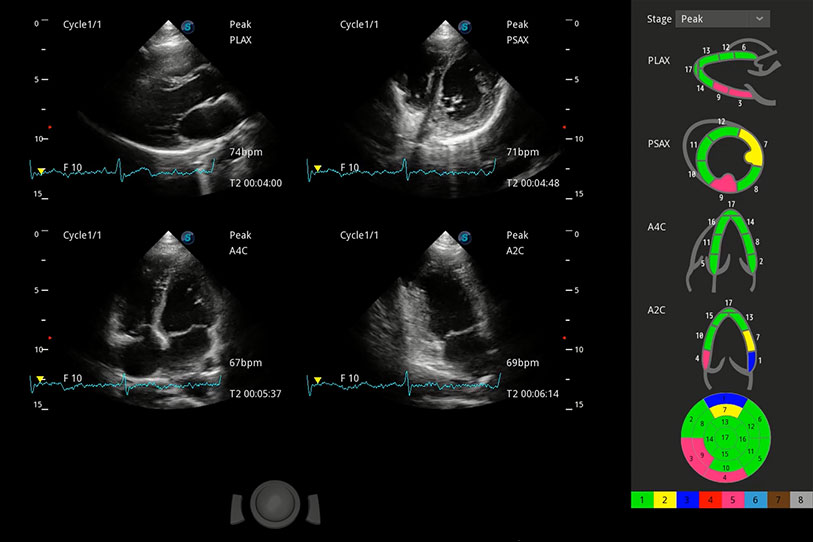

能夠基于左心室壁追蹤和辛普森法,自動(dòng)計(jì)算射血分?jǐn)?shù),支持多個(gè)可移動(dòng)點(diǎn)描跡,與手動(dòng)測(cè)量相比,極大節(jié)省了動(dòng)物醫(yī)生的時(shí)間和精力。

具備多種協(xié)議可選,同時(shí)支持17階段劃分法和專(zhuān)業(yè)的SE報(bào)告。

通過(guò)360度任意調(diào)節(jié)3條M型取樣線(xiàn),在同一心動(dòng)周期上觀(guān)察心臟不同位置的運(yùn)動(dòng)曲線(xiàn),得到準(zhǔn)確的心功能測(cè)量數(shù)據(jù),有效評(píng)估心肌運(yùn)動(dòng)及左心室功能。

實(shí)時(shí)用顏色表示心肌組織運(yùn)動(dòng),觀(guān)察和定量組織的運(yùn)動(dòng)情況,對(duì)快速檢測(cè)與評(píng)估心肌的灌注和活性、電傳導(dǎo)及心肌收縮和舒張功能等均能提供重要的診斷信息。